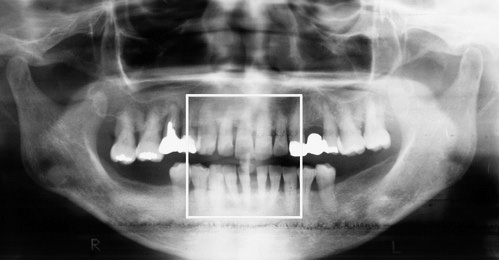

このレントゲン写真は40代の方です。

8番目が親知らずです。

横に向いて生えていますね。

親知らずの手前の歯7番目、その手前の歯6番目、どうなっているでしょう?

6番目は斜めに倒れて、かつ、上に上がっていますね。

親知らずに押し上げられているんですね。

このレントゲン写真でもう一つ重要なことが、あります。

それは、親知らずのすぐ手前の7番目の歯の根っこをご覧下さい。

歯を支えている骨が溶けているんです。

レントゲン写真というのは硬いところが白くうつります。

5番目の歯の根っこのあたりは歯の根の周りがまだもや~っと白くうつっています。

これは「骨」が写っているんです。

しかし、7番目には、骨が、ない。

さらに6番目の根っこの7番目よりのあたりまで骨が溶けています。

7番目の歯を支えている骨が全然ないのです。

6番目の歯を支えている骨が後ろ半分ないのです。

ということはこの7番目の歯はグラグラに揺れています。

抜かなければならないということです。

ほっといてもそのうち勝手に抜けます。

「親知らず」を抜かずに放置しておいたために、その「親知らず」が横に押し上に押し、さらにこの7番と8番の間に溜まったバイ菌が取りきれないわけです。

ここはどんなにご自身で歯ブラシをしても、フロスをしてもばい菌を取りきること

は出来ません。